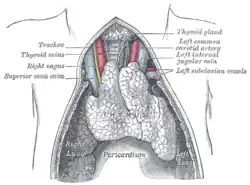

The thymus of a full-term fetus, exposed in situ

The thymus of a full-term fetus, exposed in situ -

Right Vagus Nerve: The right vagus nerve gives rise to the right recurrent laryngeal nerve, which hooks around the right subclavian artery and ascends into the neck between the trachea and esophagus. The right vagus then crosses anterior to the right subclavian artery, runs posterior to the superior vena cava, descends posterior to the right main bronchus, and contributes to cardiac, pulmonary, and esophageal plexuses. It forms the posterior vagal trunk at the lower part of the esophagus and passes through the diaphragm to enter the abdomen through the esophageal hiatus.

Left Vagus Nerve: The left vagus nerve enters the thorax between left common carotid artery and left subclavian artery and descends on the aortic arch. It gives rise to the left recurrent laryngeal nerve, which hooks around the aortic arch to the left of the ligamentum arteriosum and ascends between the trachea and esophagus. The left vagus further gives off thoracic cardiac branches, breaks up into the pulmonary plexus, continues into the esophageal plexus, and enters the abdomen as the anterior vagal trunk by way of the esophageal hiatus of the diaphragm.